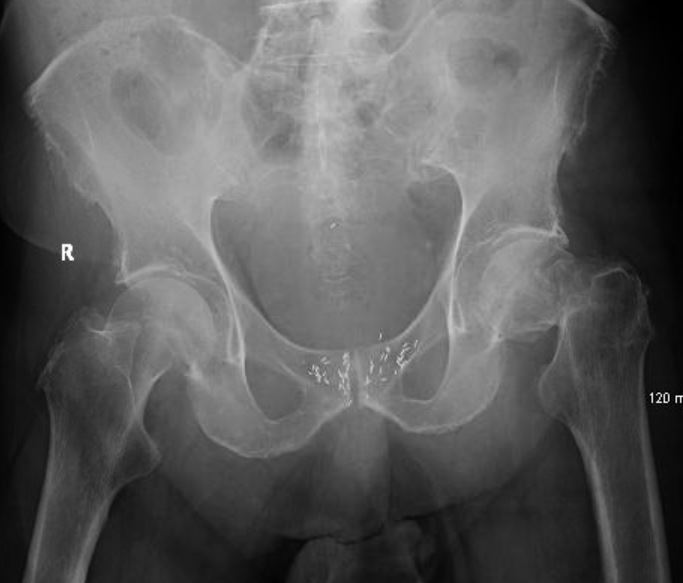

This is a case of an elderly gentleman who sustained a fall from standing height. He fractured his left hip This is classified as a displaced femoral neck fracture. See x-ray below: